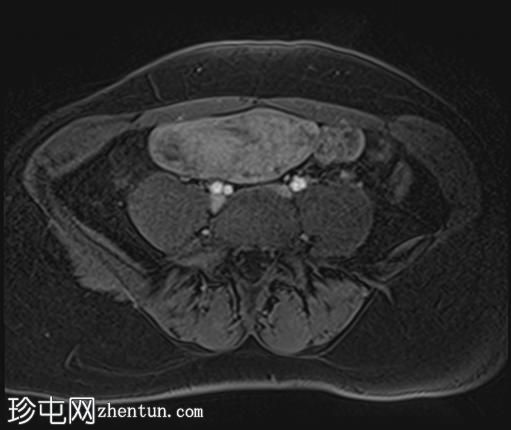

轴位T1加权像

增强脂肪抑制像

2个月前进行的MRI检查显示双侧卵巢肿块均有强化,右侧卵巢肿块未见扭转。